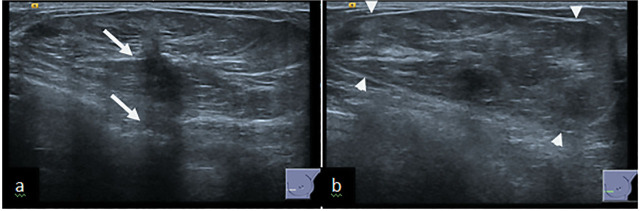

Case description: We present two cases of breast hamartoma in 51 and 61 years old female who presented to us through screening and symptomatic clinics.Both cases had imaging findings typical for diagnosis of hamartoma however there was a distortion within the hamartoma which raised possibility of malignancy and prompted a core biopsy and MDT discussion.

Practical implication: Many hamartomas have typical benign imaging appearances and require no further investigation. Biopsy is needed in atypical looking hamartomas to exclude a breast carcinoma, which although rare may develop within a hamartoma. Multidisciplinary team discussion is crucial in the management of atypical cases to ensure radiological-pathological concordance.